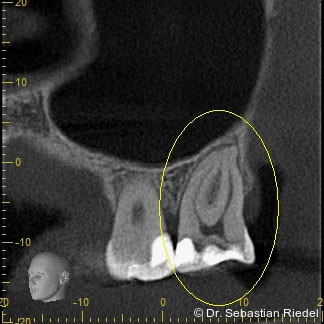

Die Präparation des Zahnes erfolgt entsprechend der anatomischen Lage der Wurzelkanaleingänge – bewährte Schemata dafür liegen vor. Die Möglichkeit der dreidimensionalen Dia­gnostik mittels DVT bietet einen zusätzlichen Schutz, um wertvolle Zahnhartsubstanz zu erhalten und trotzdem einen geradlinigen Zugang zu den Kanalorifizien zu ermöglichen.